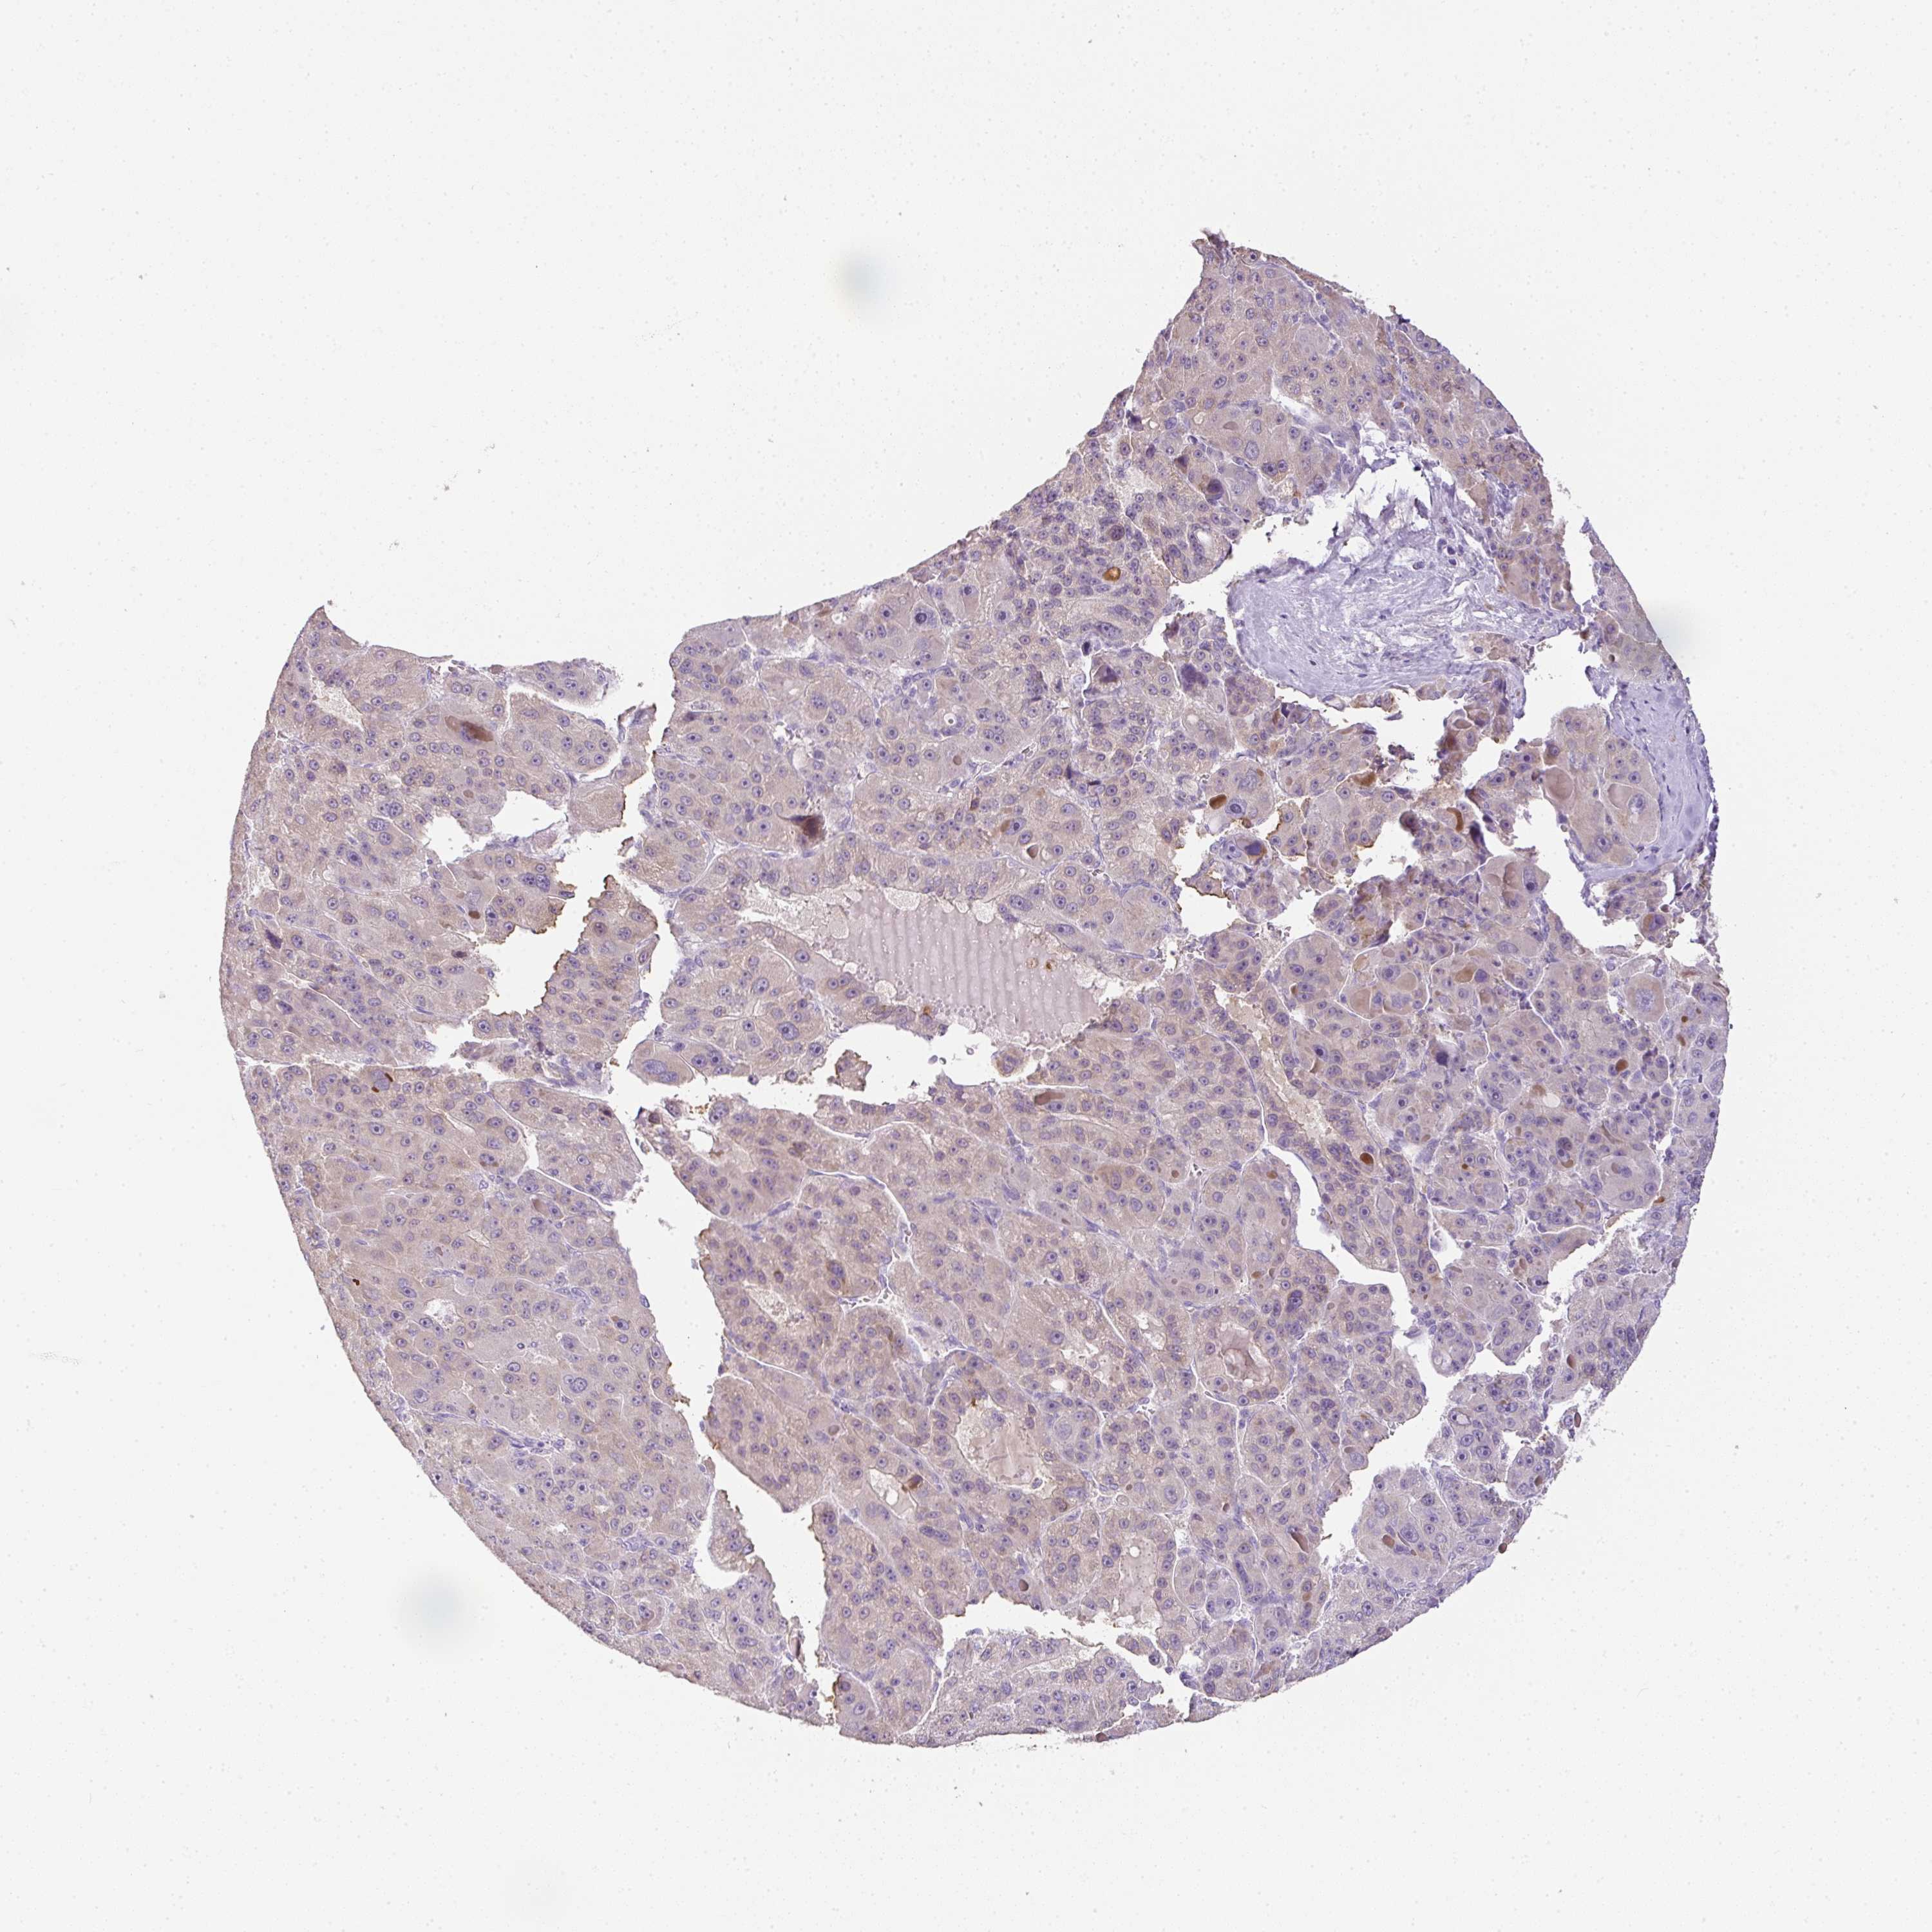

LIVER CANCER - Protein expressioni

A mouse-over function shows sample information and annotation data. Click on an image to view it in a full screen mode. Samples can be filtered based on level of antibody staining by selecting one or several of the following categories: high, medium, low and not detected. The assay and annotation is described here.

Antibody stainingi

Antibody staining in the annotated cell types in the current human tissue is reported as not detected, low, medium, or high, based on conventional immunohistochemistry profiling in selected tissues. This score is based on the combination of the staining intensity and fraction of stained cells.

Each image is clickable and will lead to virtual microscopy that enables deeper exploration of all samples and also displays staining intensity scores, fraction scores and subcellular localization as well as patient and tissue information for each sample.

Antibody HPA053730

Antibody HPA058604

Staining

High

Medium

Low

Not detected

Intensity

Strong

Moderate

Weak

Negative

Quantity

>75%

75%-25%

<25%

None

Location

Nuclear

Cytoplasmic/membranous

Cytoplasmic/membranous,nuclear

Cholangiocarcinoma

Carcinoma, Hepatocellular, NOS